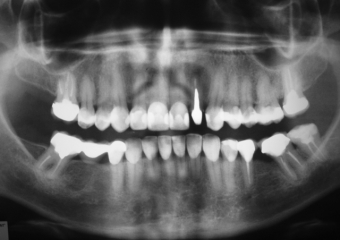

Raio X inicial apresentando ausência do molar inferior direito